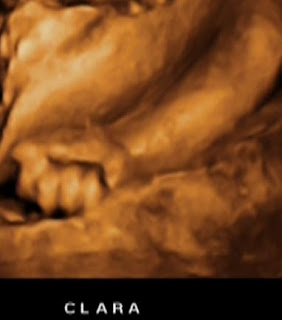

Uma das minhas mãozinhas eu coloco de vez em quando no meu rostinho.

A outra fica fechadinha do lado da minha barriguinha, bem fechadinha, igual à da bisa Alice.